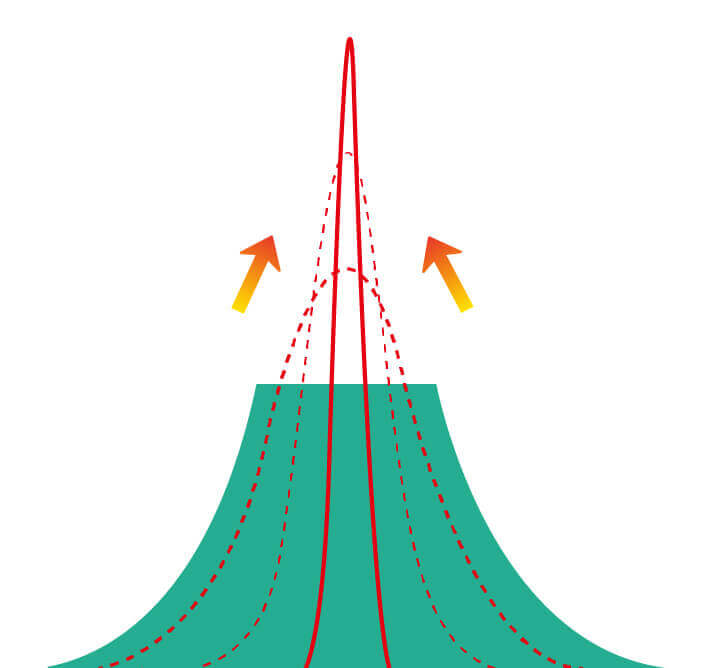

Spectral Focused lmaging, SFI

图像具有高亮度、高黏膜血管颜色对比度的特点,且不改变粘液、食物残渣、粪便的基本颜色,可在中远景下进行观察,助力消化道早期疾病的诊断。

Versatile Intelligent Staining Technology, VIST

强调浅层黏膜结构的同时,保证照明亮度和提升浅层微血管与中层血管颜色对比度,病变边界更清晰。

血管对比度分布光谱曲线

血管对比度分布光谱曲线

VIST光谱

VIST光谱

采用光路合束技术,光谱自由度高,实现了更丰富的照明模式,染色模式SFI及VIST,从远景到近景,助力消化道早期疾病诊断。